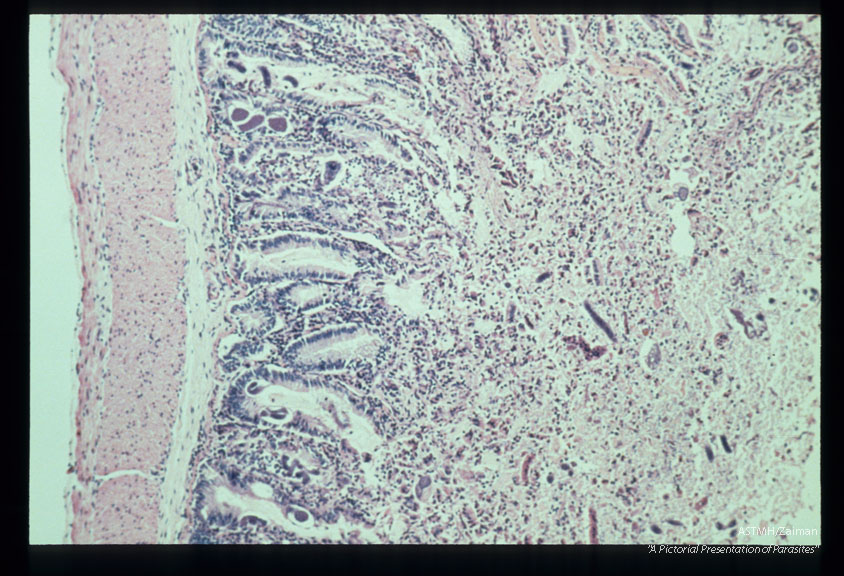

Jejunitis induced by experimental infection in Erythrocebus patas.

Strongyloides stercoralis

Description: Jejunitis induced by experimental infection in Erythrocebus patas.